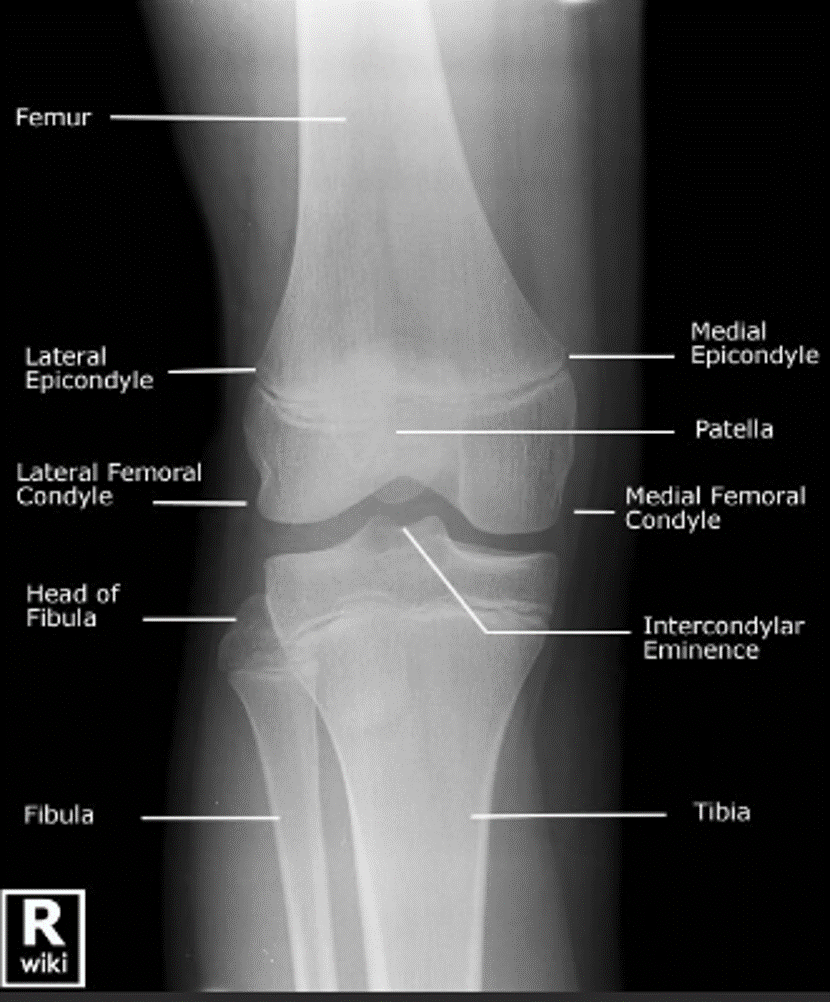

MRI and CT

A

MRI : Great for soft tissue and bone changes (infection, inflammation, necrosis, etc); taken in slices like CT; can be distorted by metal

CT : Great for seeing bone and alignment issues in multiple slices; can result in 3-D reconstruction; not great for soft tissue